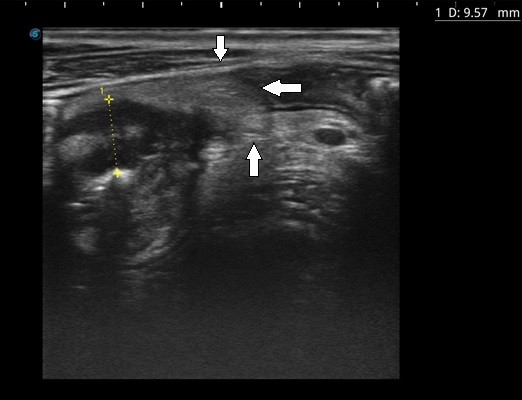

Ультразвуковые признаки болезни Крона, ультразвуковые индексы для оценки активности болезни Крона

Ультразвуковое исследование для выявления осложнений воспалительных заболеваний кишечника